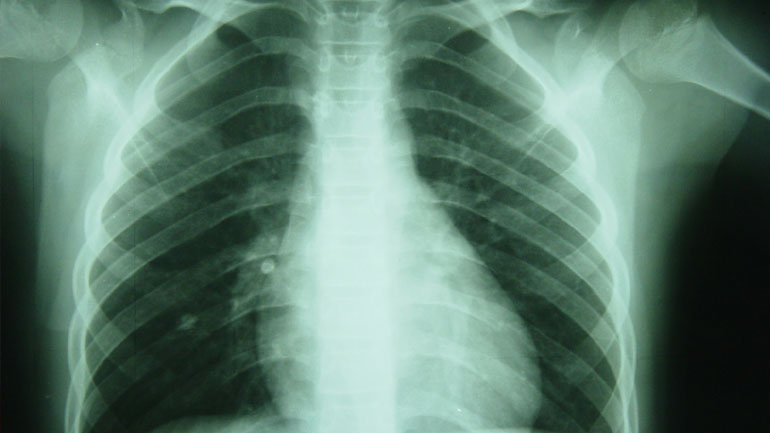

Αυξάνεται ο αριθμός των νεκρών από φυματίωση στη Ευρώπη σύμφωνα με τον ΠΟΥ

Έπειτα από δύο δεκαετίες συνεχούς υποχώρησης, ο αριθμός των νεκρών από φυματίωση αυξάνεται και πάλι στην Ευρώπη, προειδοποίησε...